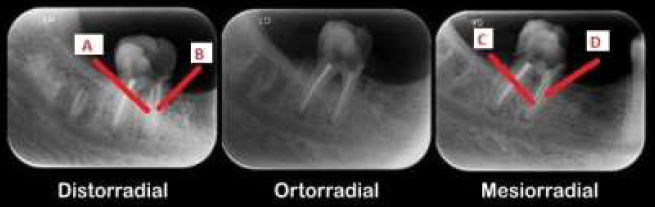

A técnica de Clark tem como objetivo identificar a localização de algumas estruturas da cavidade bucal. Analise a imagem e responda as questões 21 e 22.

I. O canal C está pela lingual e o D pela vestibular.

II. A estrutura que se encontra na frente, acompanha o movimento do feixe de raio X.

Analise as assertivas:

I. O canal A está pela lingual, enquanto o B está por vestibular.

II. O canal A está pela vestibular, enquanto o B está por lingual.

III. O canal D está pela vestibular enquanto o canal A está por vestibular.

O canal C está pela vestibular, enquanto o B está por vestibular.